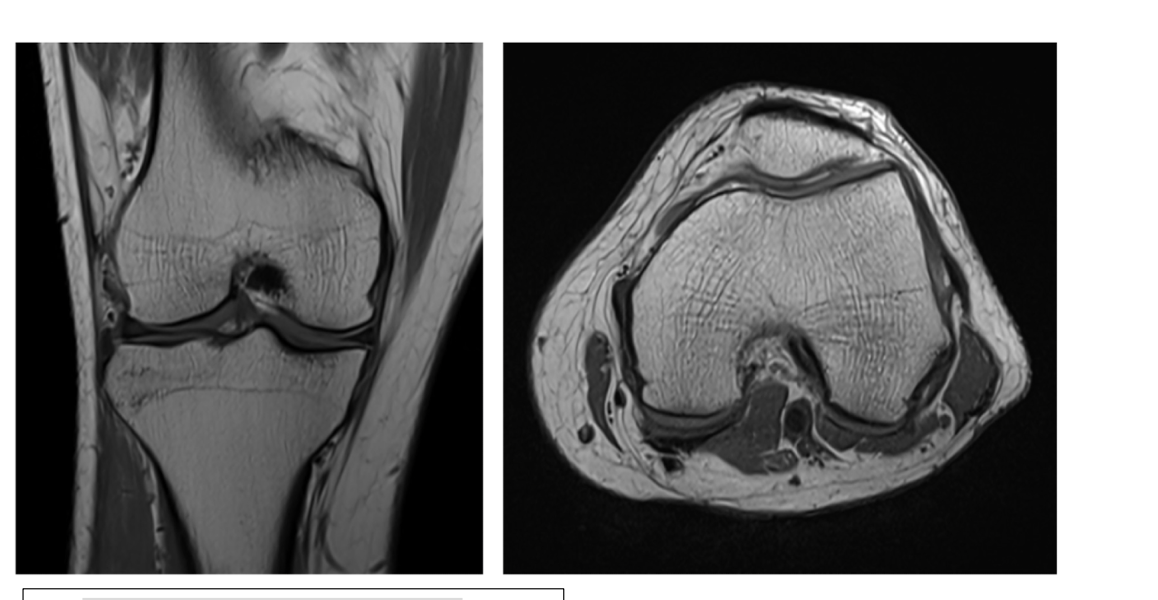

What are the sequences and what is the pathology?

label each

2- lateral and medial condyles of femur

4- vastus lateralis muscle

5-posterior cruciate ligament

6- anterior cruciate ligament

7- medial meniscus of knee

8- lateral meniscus of knee

9-tibia

10-fibula

Sequence + pathology?

• 1st = PD: intermediate signal from muscle and fat is bright, image quality is much better

• 2nd = PD FS: fat has been supressed appearing much darker

• Path = complete ACL tear: in a normal knee you would see a black band which is the acl sitting

across the anterior aspect of the tibia and extending to the posterior aspect on the femur. This is not present at all hence, a tear.